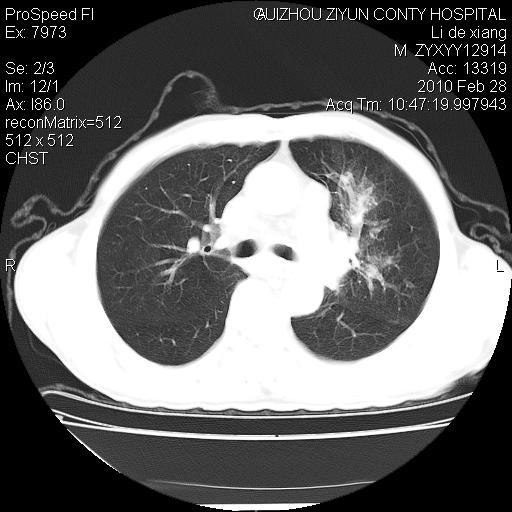

标题: CT24776:男 71Y 咳嗽咳痰胸痛两月,伴声音嘶哑。 [打印本页]

标题: CT24776:男 71Y 咳嗽咳痰胸痛两月,伴声音嘶哑。

左侧中央型肺癌伴左肺上叶阻塞性肺炎及节段性不张可能性大,建议纤支镜检查!

左侧中央型肺癌伴左肺上叶阻塞性肺炎及节段性不张可能性大,建议纤支镜检查!纵隔淋巴结转移.

左侧中央型肺癌伴左肺上叶阻塞性肺炎及纵隔淋巴结转移。

左肺门部肿块,伴左上肺斑块影,周边模糊,支持左肺中央型肺癌伴节段性不张及阻塞性肺炎,结合支气管镜检查。

左上叶支气管狭窄,阻塞性病变,肺门肿块,纵隔及肺门淋巴结增大,中央性肺癌

左肺中央型肺癌并阻塞性改变、纵膈 淋巴结转移

左侧中央型肺癌伴左肺上叶阻塞性肺炎及纵隔淋巴结转移

支持 左肺中央型肺癌伴左肺上叶阻塞性肺炎,纵隔淋巴结转移。